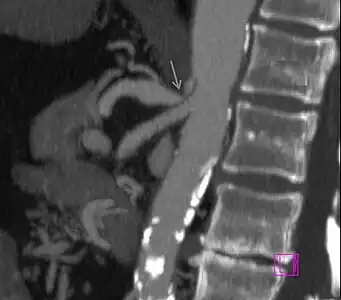

Further evaluation and confirmation can be obtained via angiography to investigate the anatomy of the celiac artery.[5] Historically, conventional angiography was used, although this has been largely replaced by less invasive techniques such as computed tomography (CT) and magnetic resonance (MR) angiography.[2][5] Because it provides better visualization of intra-abdominal structures, CT angiography is preferred to MR angiography in this setting.[5] The findings of focal narrowing of the proximal celiac artery with poststenotic dilatation, indentation on the superior aspect of the celiac artery, and a hook-shaped contour of the celiac artery support a diagnosis of MALS.[2] These imaging features are exaggerated on expiration, even in normal asymptomatic individuals without the syndrome.[2]

Proximal celiac artery stenosis with poststenotic dilatation can be seen in other conditions affecting the celiac artery.[2] The hook-shaped contour of the celiac artery is characteristic of the anatomy in MALS and helps distinguish it from other causes of celiac artery stenosis such as atherosclerosis.[2] This hooked contour is not entirely specific for MALS however, given that 10–24% of normal asymptomatic individuals have this anatomy.[2]

Median arcuate ligament syndrome-a)Stenosis and aneurysm of celiac artery because of compression arrows b)severe stenosis and poststenotic dilatation white arrow c) median arcuate ligaments arrows and gastric mucasal thickening